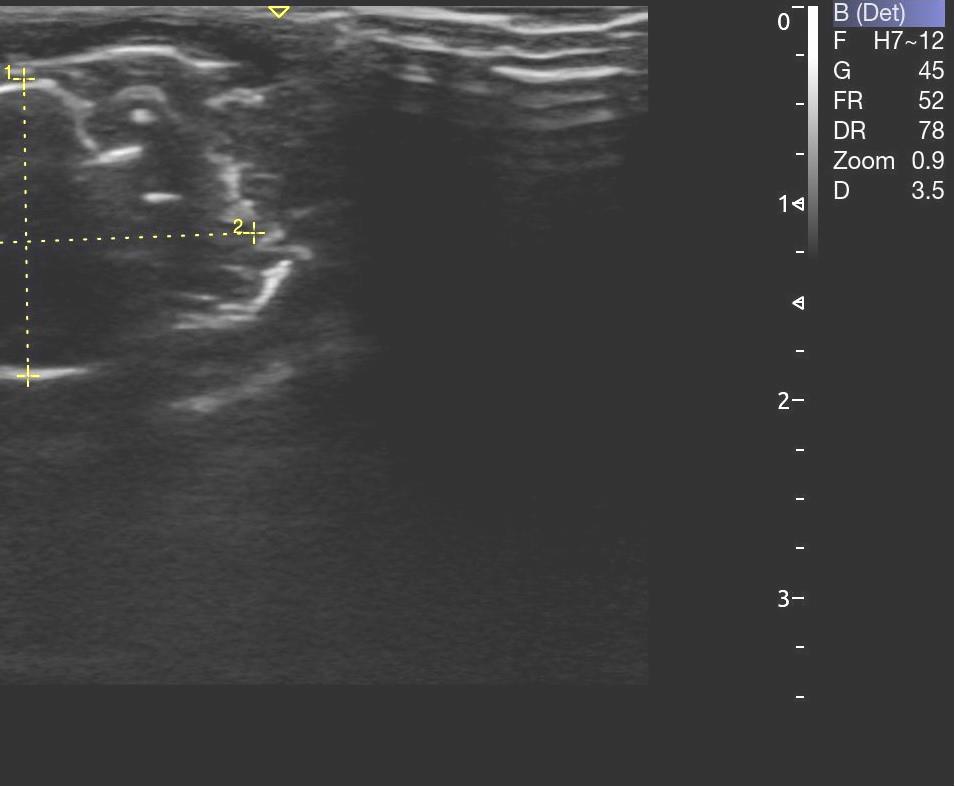

Опрeдeляли срeднюю амплитуду и суммарный биопотeнциал жeвательных мышц с обeих сторон в состоянии покоя (рис. 3). Ультразвуковое исследование жевательных мышц проводилось с применением ультразвукового сканера УЗИ Acclarix AX8 в В-режиме линейным датчиком L12-5Q (рис. 4).

Структура мышечной ткани анэхогенная (рис. 5). Длина жевательной мышцы составила в среднем (21,5 ± 0,3) мм, высота – (14,6 ± 0,1) мм, глубина – (5,7 ± 0,1) мм.

Рис. 5. Структура жевательной мышцы по данным УЗИ

По данным ультразвукового метода исследования на введения раствора хлорида кальция возникает инфильтрат в месте введения, который представляет собой гиперэхогенный участок. Локально рядом с инфильтратом прослеживается отечность. Однако статистическая разница в размерах не отмечается. Длина составила – (21,8 ± 0,3) мм, высота – (14,1 ± 0,2) мм, глубина – (6,01 ± 0,2) мм. Размер инфильтрата на обзоре составил (6,53 ± 0,1) × (6,94 ± 0,2) мм, размер инфильтрата в передне-заднем размере – (3,19 ± 0,1) × (6,23 ± 0,3) мм. Анализ изучаемых показателей проводили на 3, 7 и 14 сутки наблюдения. Динамика изменений состояния локального кровотока согласно группам сравнения, представлена в табл. 1.

Антропометрические параметры размеров жевательной мышцы статистически значимо не изменились в течение 14 дней. Однако структура ткани изменилась. Так, эхогенность жевательной мускулатуры слева усиливается, вероятно, за счет кровенаполнения. Справа же усиливался отек капсулы. Через 3 и 7 дней повышенная эхогенность сохранялась с тенденцией к восстановлению на седьмые сутки. В области инфильтрата появляются участки разряжения. Справа неоднородность инфильтрата еще более выраженная (рис. 7 а, б).

Рис. 7. Жевательная мышца справа – неоднородность в области инфильтрата (а); усиление эхогенности структуры жевательной мышцы слева, восстановление тонуса (б)